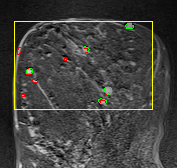

In MR images, tumor regions are normally brighter and have more uniform intensity than the neighbouring healthy tissue. Based on this fact, we determined the internal and external markers by sorting out the pixel values in ROIs in descending order and chose pixels with maximum intensity values as markers. After selecting the markers the normal watershed transformation is applied on the ROIs image which is shown in Fig 1 Finally, a binary mask is generated based on watershed output regions. However, we identified the optimal number of markers based on segmentation accuracy evaluated using Dice and Jaccard.

We tested the algorithm by varying the number of markers between and . Fig 2 describes the segmentation results obtained using different numbers of markers. This plot indicates that markers were found to be optimal using this segmentation approach, yielding satisfactory results.

where refers to the ROIs segmented by our algorithm and is tumor area as determined by manual segmentation. Table 1 summarizes the segmentation accuracy achieved using the proposed method for all 106 cases. The average dice coefficient was found to be 0.780.17 and average Jaccard index was 0.670.21. Fig 3 demonstrate four sample segmentation outputs which are overlaid on manual segmentations provided by two radiologists. It can be seen, that the proposed method could accurately segment the lesions with some marginal errors for medium to large tumors. However, for cases comprising disjoint lesions, the method failed to segment all small lesions and in some cases incorrectly labeled healthy tissue as lesions. This is because in some cases there is a high degree of overlap in the intensity distributions of healthy breast tissue and lesions, and the ROI drawn by the radiologist is very large in the case of disjoint lesions, in order to cover the entire area over which multiple lesions are distributed.